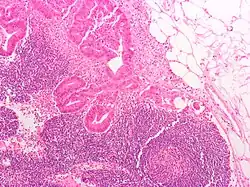

Micrograph of a mesenteric lymph node with adenocarcinoma

Lymph nodes can be affected by both primary cancers of lymph tissue, and secondary cancers affecting other parts of the body. Primary cancers of lymph tissue are called lymphomas and include Hodgkin lymphoma and non-Hodgkin lymphoma.[35] Cancer of lymph nodes can cause a wide range of symptoms from painless long-term slowly growing swelling to sudden, rapid enlargement over days or weeks, with symptoms depending on the grade of the tumour.[35] Most lymphomas are tumours of B-cells.[35] Lymphoma is managed by haematologists and oncologists.

Local cancer in many parts of the body can cause lymph nodes to enlarge because of tumorous cells that have metastasised into the node.[36] Lymph node involvement is often a key part in the diagnosis and treatment of cancer, acting as "sentinels" of local disease, incorporated into TNM staging and other cancer staging systems. As part of the investigations or workup for cancer, lymph nodes may be imaged or even surgically removed. If removed, the lymph node will be stained and examined under a microscope by a pathologist to determine if there is evidence of cells that appear cancerous (i.e. have metastasized into the node). The staging of the cancer, and therefore the treatment approach and prognosis, is predicated on the presence of node metastases.